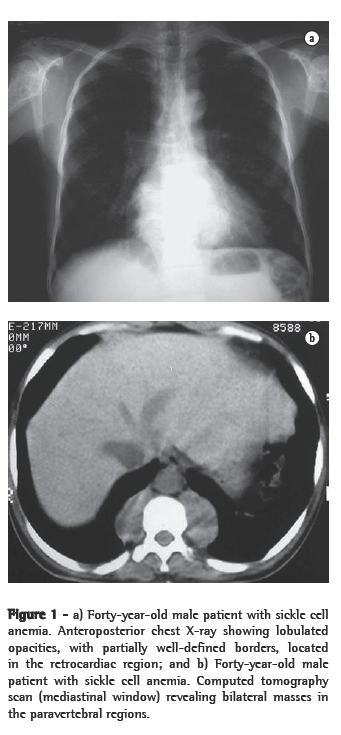

Of the six patients evaluated, four presented lower paravertebral masses. In three cases, the masses were bilateral and relatively symmetric, and, in one, the mass was unilateral (on the right). Regarding the content of the masses, the presence of adipose tissue was confirmed in three patients, and, in one of them, the quantity of adipose material was quite significant. In one patient, the masses were homogeneous, with dense soft parts (Figures 1a, 1b, 2a and 2b).

Thoracic involvement in EMH is rare.(1,5) When it occurs, it usually manifests as round, lobulated masses, with dense soft parts in the posterior mediastinum, being more common in the lower paravertebral regions.(1,2,4,5,9) Occasionally, those masses can appear in the anterior mediastinum or in the pleura.(4) Pleural effusion has been reported.(2,13) Four of our patients presented lower paravertebral masses, and two presented parietal pleural masses.

Radiographically, intrathoracic EMH usually presents as multiple paravertebral masses, with dense soft parts, usually bilateral, lobulated, with well-defined borders, and without accompanying calcifications or bone erosion.(1,4,5,9) This is important for the differential diagnosis of paravertebral neurofibromas, which usually have accompanying bone alterations.(4,10) However, evidence of bone lesions related to the underlying disease is a common finding. On chest X-rays, such masses usually present an aspect of lobulated, double-contour cardiac silhouette in frontal view, as well as an aspect of a lobulated mass projected over the lower vertebral bodies in profile.(13)